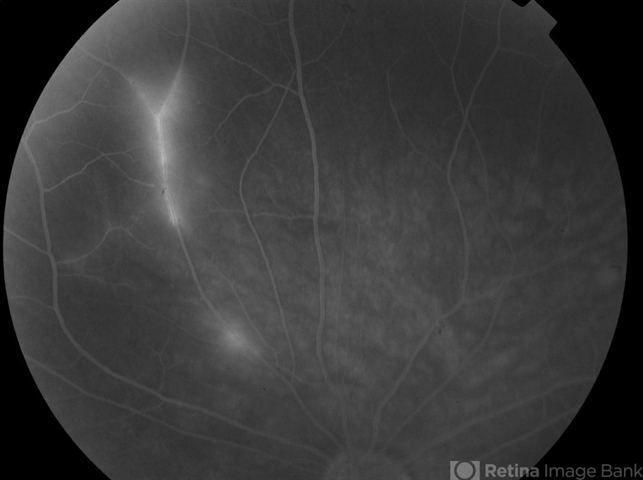

- Susac Syndrome

- Susac's syndrome, retinal vasculitis

- Background: 46-year-old WF with CML (stable on Sprycel) saw her PCP for headaches without known cause; Headaches worsened and became confused, disoriented, off balance, and impaired short term memory. Heme-oncology ordered MRI that showed abnormal signal in the cerebellum and other parts of the brain, and LP has elevated protein. LP did show positive tau test, but fortunately, was a false positive for CJD. IV and PO steroids started and symptoms improved. MRI showed much improvement one month since starting steroids. 3 weeks later had a scotoma in right eye and eye doctor did not find anything at that time to cause it. Tinnitus developed (and some intermittent vertigo before that) and ENT referred back to eye doctor, who then referred the patient to Dr. Zocchi. He found a CWS and BRAO OD, and bilateral arteritis. She had some additional work-up for vasculitis. Given the retinal arteritis, cochlear issues, and MRI findings, Dr.Zocchi suspected Susac's Syndrome. She was started on multiple regimens including prednisone, IVIG, azathiprine, and MTX, and has had the best reponse to IVIG (FA shows a recurrence/worsening while adjusting IMT). She is stable and doing well with 20/20 vision in both eyes.